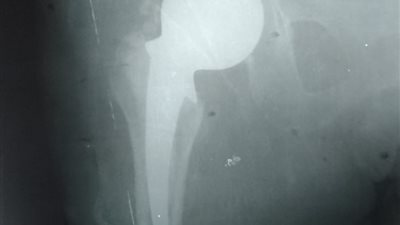

تركيب مفصل صناعي لمريضة تبلغ من العمر 67 عاما بقنا